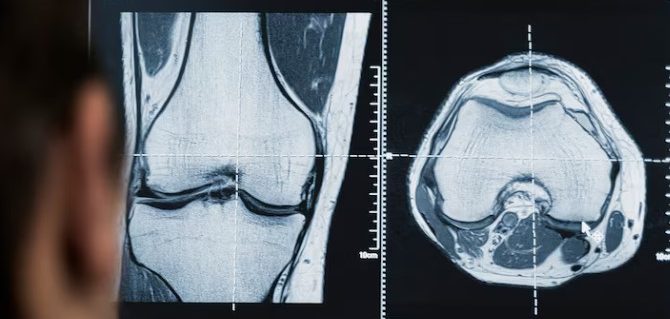

Une consultation est recommandée en cas de douleurs persistantes du dos, des hanches, des genoux ou des épaules, ainsi qu’après un traumatisme. Un examen orthopédique permet d’identifier l’origine de la douleur et d’établir un plan de suivi. La prise en charge vise la récupération fonctionnelle, la prévention et l’adaptation des activités. Notre spécialiste responsable, le Dr Filippo-Franco Schiapparelli intègre les contraintes professionnelles et familiales pour un suivi personnalisé.

- Analyse clinique et causes mécaniques/inflammatoires

Crissier combine activité professionnelle intense et mobilité quotidienne. Les douleurs articulaires peuvent limiter la capacité à travailler ou à se déplacer. Au sein du CMGR, le Dr Filippo-Franco Schiapparelli met l’accent sur l’évaluation fonctionnelle, l’identification des gestes à risque et la planification d’un suivi progressif.

- Orientation vers examens complémentaires